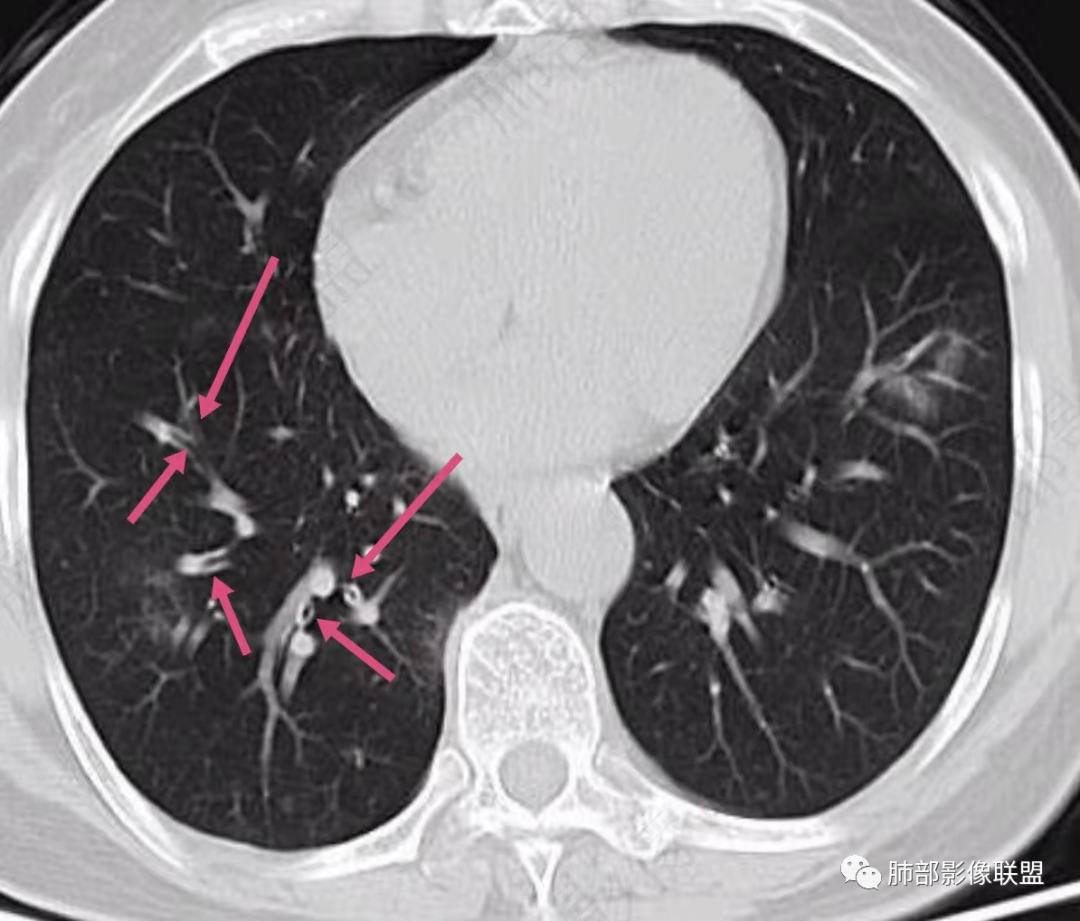

2、CT表现为两肺下叶结节影、斑片影、磨玻璃影,沿支气管血管束分布,部分支气管壁显示增厚。粗略一看部分病灶内似可见“细网格影”,但是仔细观察,可发现此“细网格影”不同于我们常见的“细网格影”,尤其是右肺下叶病灶,可以观察到病灶内部的网格上有高密度结节感或颗粒感,部分层面见“反晕征”,且反晕的边缘亦可观察到结节感。未见胸腔积液。

2、但影像学具有一定的特征性,病变一般沿支气管树分布或小叶分布,一般上肺多于下肺。部分病例呈双肺“雪花样”分布,较有特点。部分病例可表现为“反晕征”。除以上表现外,间质性肺结核还可以表现为:1 肺小叶间质内异常,表现为小叶间质内网状影,呈网结节样改变,与正常肺分界较清晰是其特点。2 支气管血管束增粗和小叶间隔增厚。3 磨玻璃影。

2、好发部位与其它结核类似,上叶及下叶背段为主。 3、烟花征,反晕征,环呈结节状,可以伴随空洞,树芽征,结节灶,胸水。(反晕征:一般周围实性环形高密度影,中央呈低密度;一般环超过圆的3/4,结核的环主要是小叶核心结节组成,类似于多发树芽征聚集,边缘结节感。中央的晕:可以是腺泡结节,树芽征,细网状,磨玻璃影,很少正常,主要成分是小叶内间质增厚、小叶核心结节、肺泡内病变。)其实也体现了结核的多灶性、多态性特点。

4、其实不一定完全表现为反晕征,还有比较密集的烟花,聚集成团,与反晕征同在。